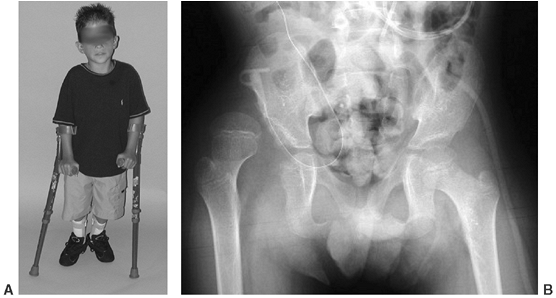

and L-4 level of motor function have a reasonably good chance for

functional walking because of the presence of power in the medial

hamstrings, which can act as hip extensors (91,106,111,112) (Fig. 16.4).

![]() |

|

Figure 16.4

Community-ambulatory child with L-3–L-4 level of function. He uses Lofstrand crutches and bilateral ankle-foot orthoses. He is able to ambulate with a swing-through gait despite a unilaterally dislocated hip. (Courtesy of Charles T. Price, MD) |